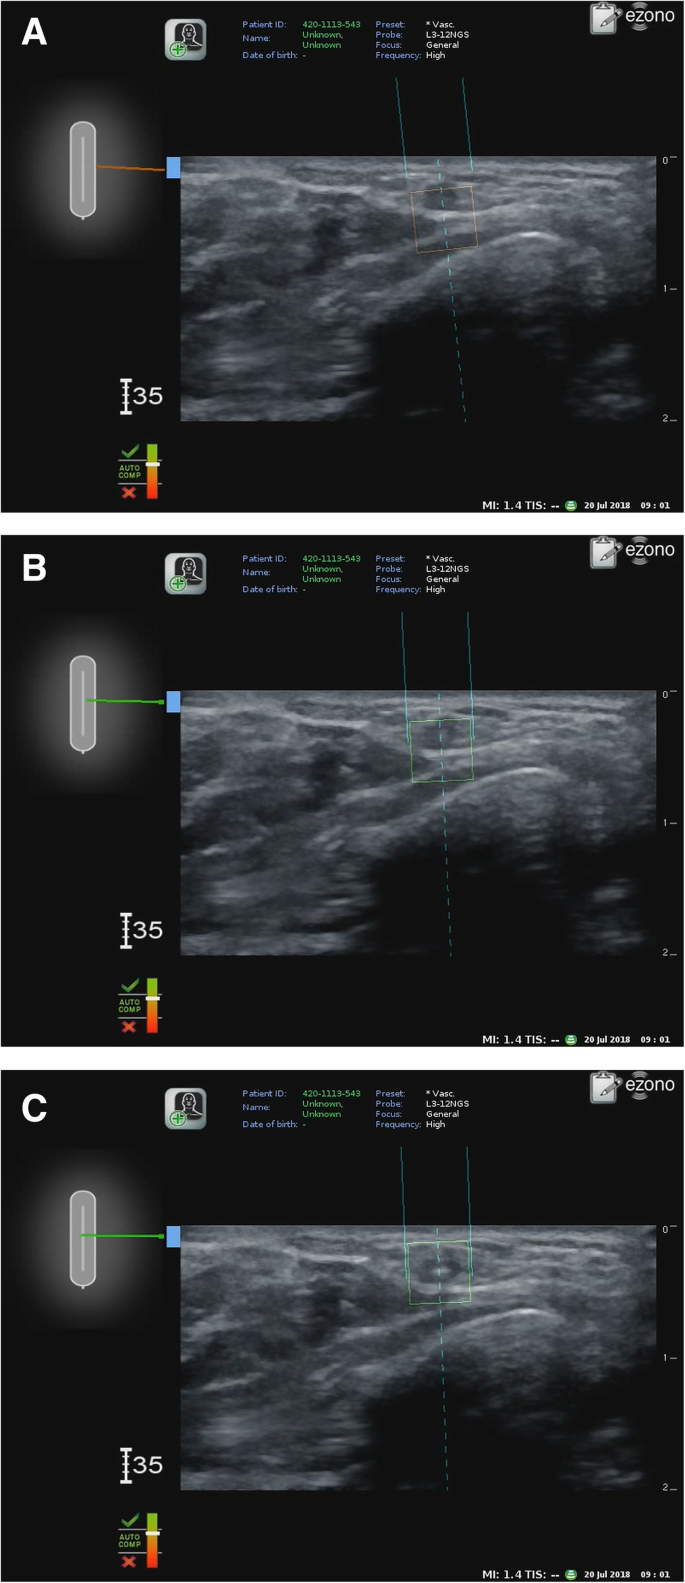

In group E, the electromagnetic guidance system (eZono 4000, eZono AG, Jena, Germany) was turned on, and a linear probe (3–12 MHz, NGS linear transducer, eZono AG) was placed perpendicular to the radial artery to obtain a short-axis view. After magnetizing the needle, the provider punctured the skin and inserted the needle perpendicular to the long axis of the probe—the out-of-plane approach—while maintaining an optimal view on the screen. The screen showed the expected route of the needle as a dotted line, the actual position of the needle as two solid lines, and the expected tip of the needle as a square box (the indicator box). The location and direction of the needle relative to the probe were shown in the upper left screen, and the needle changed in appearance on the screen from red to green when its tip reached the plane of the long axis of the probe (Fig. 1). The provider then advanced the needle toward the radial artery until the needle in the upper left screen appeared green while adjusting the needle direction to maintain the dotted line and the square indicator box targeting the radial artery in the correct orientation on the screen. The puncture of the radial artery by the needle was confirmed by the occult blood that appeared in the needle. In group C, radial artery cannulation was performed using the conventional technique under ultrasound guidance [7], which is the same technique as that used in group E except that no electromagnetic guidance was used during the procedure. If the provider failed to puncture the radial artery, the needle was removed, and the procedure was attempted again.

a. Radial artery cannulation using electromagnetic guidance system — Before alignment. The screen shows the actual position (two solid lines), expected route (dotted line), and tip of the needle (the indicator box). b. After alignment. The indicator box changed from red to green after the alignment of the needle. c. After puncture. The actual tip of the needle appeared in the middle of the indicator box